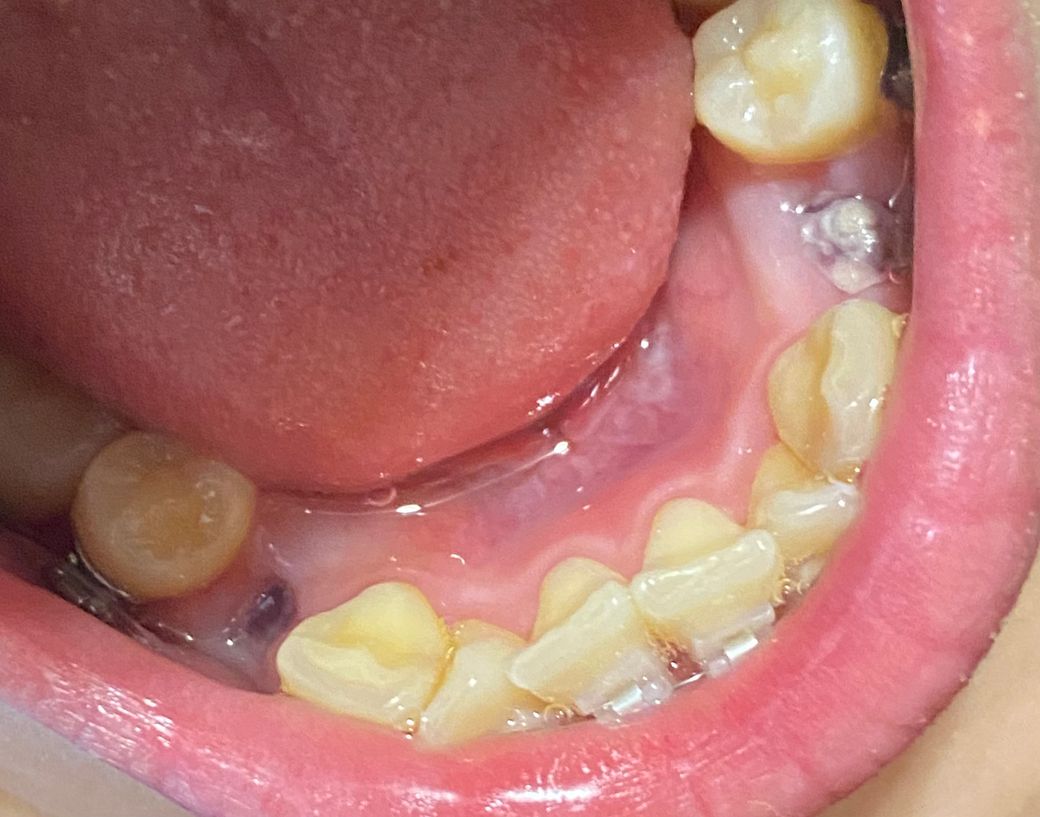

그런데 다른 세 곳은 괜찮은데 한 곳만 딱지가 조금 이상하게 생겨서 혹시나 드라이소켓인가 걱정이 되네요..ㅠㅠ

검은색은 없고 빨간 피떡 위에 흰색 딱지가 덮여있는 것처럼 생겼습니다

드라이소켓은 통증이 엄청 심하다고 하는데 저는 통증이 하나도 없고 밥도 잘 먹고 양치도 잘 했거든요

• 2번 째 사진

드라이 소켓은 감염이 일어나서 발생하는걸로 통증도 심하고 냄새도 심하게 납니다. 드라이 소켓은 아닌거 같습니다.

해당부위에 통증이 심하거나 냄새가 나지 않는다면 그냥 혈병이 생긴것으로 보입니다.

크게 문제가 되지는 않을것으로 보이나 발치된 부위가 자극이 되지 않도록 하는것이 좋습니다.

낫는 과정에서 잇몸이 하얗게 덮입니다. 일주일 정도 지났고 통증이 없으면 드라이소켓 가능성은 거의 없습니다.